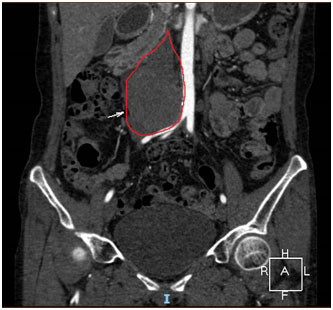

张女士的盆腹腔血管三维重建

盆腹腔血管三维重建明确病灶与腹主动脉、下腔静脉、输尿管的关系都很密切,尤其与下降静脉的分界欠清,不排除侵犯下腔静脉血管的可能。妇科何善阳主任、肝移植病区巫林伟主任、泌尿外科毕学成主任、麻醉科王越洪主任等共同讨论:恶性肿瘤侵犯大血管的可能性很小,多为外压性改变,但不排除粘连致密,难以分离导致血管破裂。动脉管壁较厚,常常好分离,反而下腔静脉管壁薄,容易破裂,若为小破口,则行血管修补;若破口较大,无法修补,则需要行人工血管置换术,因此切除肿物前要先游离下腔静脉上下方足够位置,必要时阻断血管,完整切除病灶。患者影像学检查提示右肾、输尿管积水,考虑肿瘤压迫引起,术前最好留置输尿管支架(双J管)以防止术中损伤输尿管。专家们认为手术风险大、难度高,手术前要充分备血、手术室做好血管置换的准备、保证麻醉肌松效果、手术中生命体征平稳、手术后转入ICU监护。